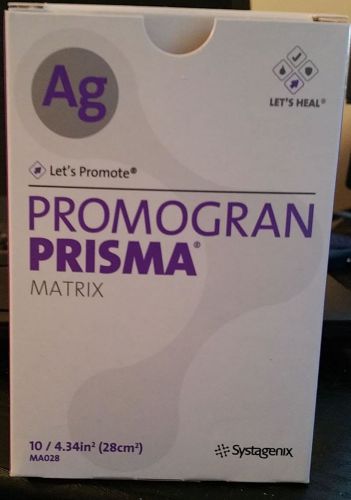

PROMOGRAN PRISMA AG MATRIX 4.34" 10/BX #MA028 SYSTAGENIX BOX: PLUS 2 EXTRA!!

PROMOGRAN PRISMA AG MATRIX 4.34" 10/BX #MA028 SYSTAGENIX: Expires 2/17